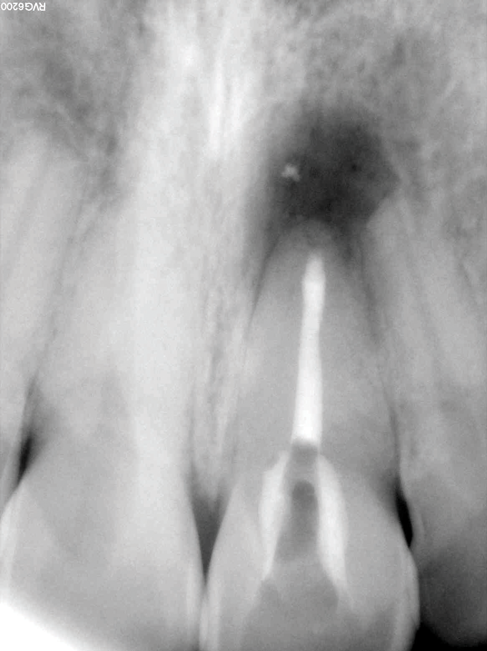

(9.) Preoperative radiograph of previously treated tooth No. 9, which received a diagnosis of acute apical abscess secondary to childhood trauma and recurrent endodontic pathology.

Figure 9

(10.) Posttreatment radiograph and cone-beam computed tomography (CBCT) scan following nonsurgical root canal re-treatment that resulted in incomplete resolution of symptoms in response to percussion and palpation.

Figure 10

(11.) Posttreatment radiograph and cone-beam computed tomography (CBCT) scan following nonsurgical root canal re-treatment that resulted in incomplete resolution of symptoms in response to percussion and palpation.

(12.) Postoperative radiograph after apical surgery was performed using MTA as an apical retrofilling material.

(13.) Normal healing was noted clinically and radiographically at the 6-month follow-up appointment.